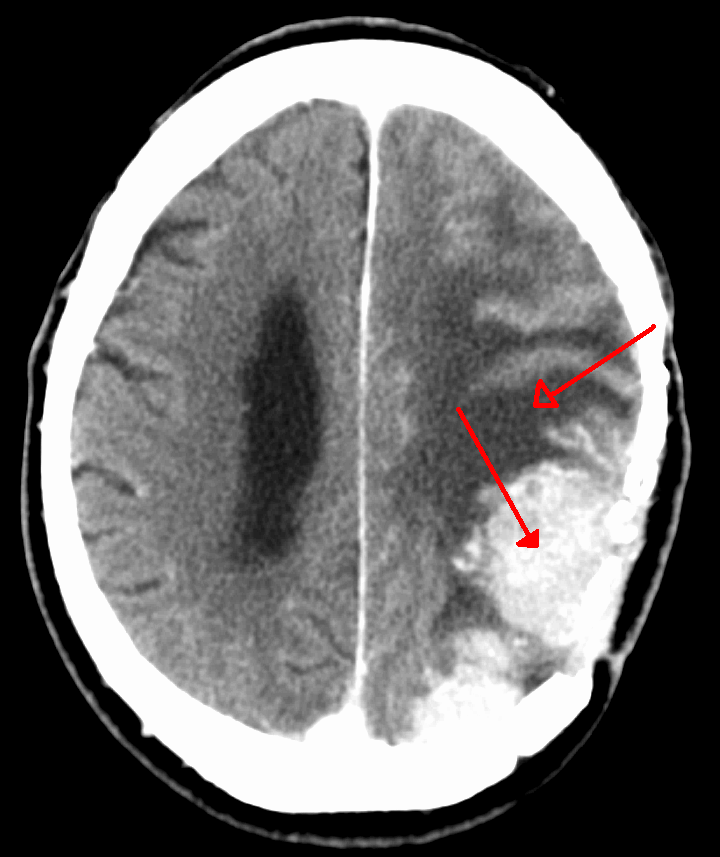

Glioblastoma multiforme (GBM) is a malignant, high-grade tumor of astrocytes.

Glioblastoma multiforme (GBM) is the most common primary malignant central nervous system (CNS) tumor in adults.

The cerebral hemisphere is where the “butterfly” lesion associated with glioblastoma multiforme (GBM), which often spans the corpus callosum, develops.

Histologically, glioblastoma multiforme (GBM) tumor cells are glial fibrillary acidic protein (GFAP) positive and are characterized by areas of necrosis surrounded by proliferating endothelial cells.

Glioblastoma multiforme (GBM) has a poor prognosis.